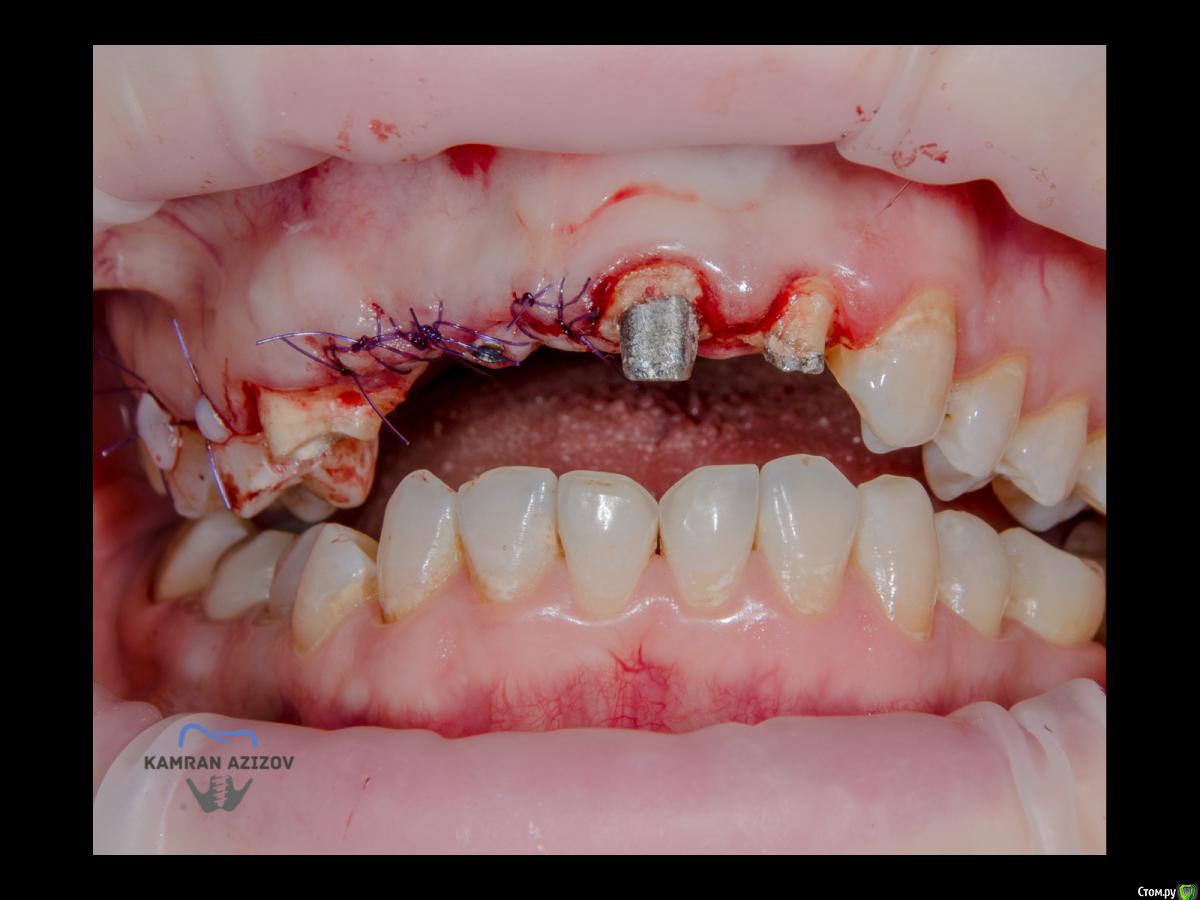

kamranchick Опубликовано 6 апреля, 2019 Поделиться Опубликовано 6 апреля, 2019 (изменено) Хай Гайсдавно ничего не комментировал и не выкладывал, что то настроения не было, да и муза не посещалаСитуация следующаяпришла пациентка, жалобы на неприятный запах из рта, сначала не понял что за хрень, ну как распилил мост понял че к чему... халтура.Ну и по кейсуУдаление клыка и 2ки, через 2 месяца навигация, имплантация + Шашлыки по карлоссу, смена формиков, временное протезирование. только мягкие ткани, Изменено 6 апреля, 2019 пользователем kamranchick 7 1 Ссылка на комментарий

kamranchick Опубликовано 6 апреля, 2019 Автор Поделиться Опубликовано 6 апреля, 2019 Тут на форуме был, ну и для многих остаётся в сердцах и головах доктор CarlossЛибо Дядя Карлен)Он делился интересными и не совсем понятными( на тот момент для многих) кейсами.И одни из работ были насаживании мягкотканного графта(сст) на фдм.А потом уже пошли Техники пончо, гамборнены, и т дК большой радости Большой зелёный( администратор) создал тему работы доктора Карлосса: там много что интересного есть, не поленись, посмотри. Много что можно на вооружение взять. Ссылка на комментарий